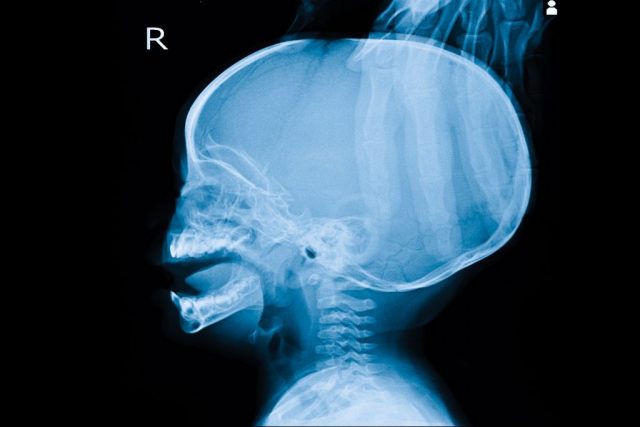

Conocemos como hidrocefalia al fenómeno por el cual se acumula una gran cantidad de líquido cefalorraquídeo en las cavidades cerebrales conocidas como ventrículos. Al darse este exceso de líquido los ventrículos crecen en tamaño y provocan mayor presión sobre el cerebro.

Este líquido, por norma general, recorre los ventrículos cerebrales y baña tanto la médula espinal como el cerebro. Sin embargo, cuando este líquido es excesivo o se concentra excesivamente en los ventrículos, puede terminar por provocar una presión excesiva sobre el cerebro que dañe los tejidos e incluso llegue a causar alteraciones cerebrales

Por norma general la hidrocefalia se da de forma mayoritaria en niños y personas mayores. Sin embargo puede desarrollarse en prácticamente cualquier rango de edad.